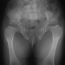

Hip dislocation and hip dysplasia have been reported, respectively

in 22% and 70% of patients. Delayed femoral head appearing, coxa valga

or, on the contrary, coxa vara are common findings.

- Long bones: they are broad and short. Metaphyses are flared and expanded.

A chevron-like shape is often present in femoral and tibial metaphyses.

Epiphyseal centers appear late and are severely irregular and flat. Ulna

and fibula are usually short.